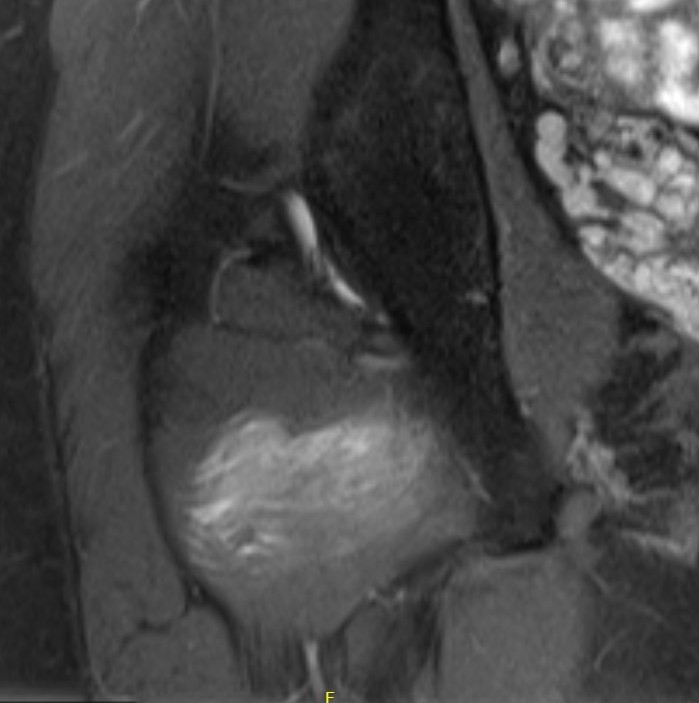

MRI

Reduced ischiofemoral space - distance between the lesser trochanter and the ischial tuberosity

Reduced quadratus femoris space - distance between hamstring tendon and iliopsoas

Inflammation / edema in quadratus femoris +/- fatty degeneration

Singer et al Skeletal Radiol 2015

- systematic review of 190 hip MRI of patients with ischiofemoral impingement

- compared to controls

- ischiofemoral space < 15 mm: sensitivity  77%, specificity 81%, accuracy 78%

- ischiofemoral space < 10 mm: sensitivity 79%, specificity 74%, accuracy 77%.